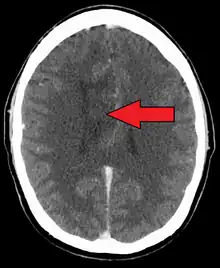

A oligoastrocytoma on CT | |

An X-ray computed tomography (CT) or magnetic resonance imaging (MRI) scan is necessary to characterize the anatomy of this tumor as to size, location, and its heter/homogeneity. However, final diagnosis of this tumor, like most tumors, relies on histopathologic examination (biopsy examination).[3]